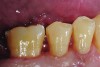

Fig 9 and Fig 10. After GIC was manually condensed and shaped, a nanofilled resin glaze was liberally applied to the surface of the finished restoration (Fig 9) and light-cured (Fig 10).

Fig 11. Completed bulk-filled GIC restorations showing excellent esthetics and surface smoothness.